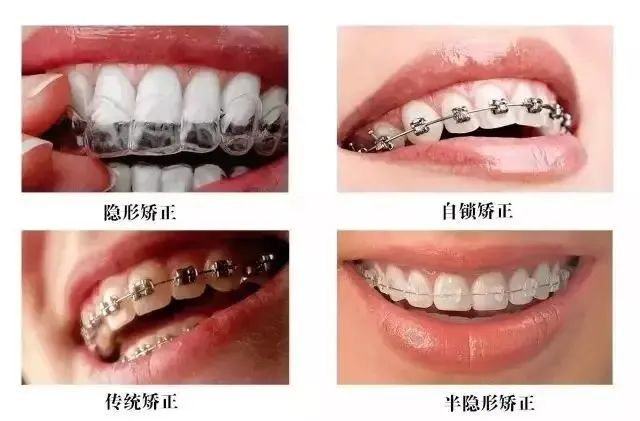

咬合关系不佳等问题都需要解决,最常见的方式是固定矫正即“戴牙套”,

现在矫治器种类也多种多样,根据不同的需要可以选择。